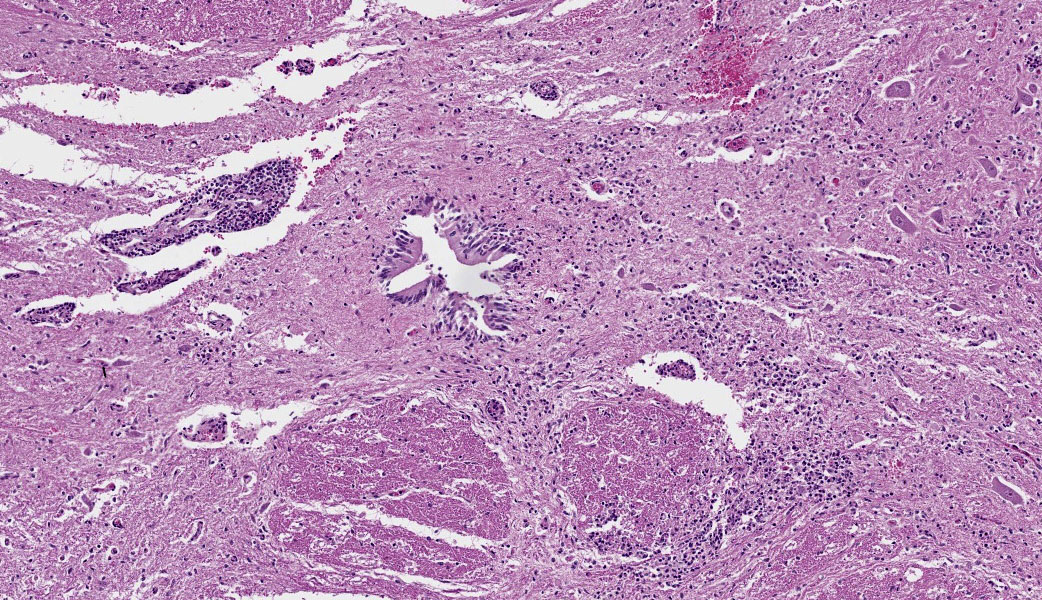

Brain, cerebellum and brainstem: In the brainstem gray matter, there are random multifocal, mild to moderate, variably discrete, infiltrates of hypersegmented and fragmented neutrophils, admixed with fewer mononuclear cells, consistent with microabscesses. Brainstem neurons within and adjacent to the neutrophilic infiltrates are pale, with central chromatolysis, consistent with neuronal degeneration. There are scattered microglial cells, mild gray matter spongiosis and infrequent microhemorrhages. Scattered blood vessels are lined by plump endothelial cells and have perivascular mild infiltrates of predominantly lymphocytes, with fewer neutrophils (perivascular cuffs). The cerebellar leptomeninges are multifocally, mildly infiltrated by predominantly lymphocytes, with fewer admixed neutrophils.

Cervical spinal cord: In the gray matter and white matter, there are scattered, variably discrete, random multifocal, mild to moderate, infiltrates of neutrophils and mononuclear cells, consistent with microabscesses. There is neuronal degeneration, spongiosis, microgliosis, and swollen axons. Blood vessels are lined by plump endothelial cells and have perivascular mild to moderate infiltrates of predominantly lymphocytes, with fewer admixed neutrophils and infrequent plasma cells. The leptomeninges are multifocally expanded by mild to moderate infiltrates of lymphocytes with infrequent admixed neutrophils.

A replicate section was examined by tissue Gram stain. There were low numbers of gram-positive bacilli, some intracellular, within areas of inflammation. A replicate section was examined by immunohistochemistry, using a rabbit polyclonal anti Listeria monocytogenes antibody (#DF2302-50-0, Fisher Scientific, Houston, TX, USA), at a dilution of 1 :2000, using the Dako Envision system (Dako Agilent Pathology Solutions, Carpinteria, CA, USA), via an indirect immunoperoxidase procedure. Within the microabscesses in the brain and cervical spinal cord, there were a low to moderate number of bacteria that bound to the primary antibody. The microscopic findings in the central nervous system accounted for the clinical signs in this sheep. The microscopic findings were typical of listeric encephalitis in ruminant species and the diagnosis was confirmed by immunohistochemistry.

There are few or no gross lesions in listeric encephalitis. Leptomeningeal opacity and cloudy cerebrospinal fluid may be the only findings seen at necropsy. Typically, microscopic lesions of listeric encephalitis are limited to the brainstem and cervical spinal cord. They include microabscesses, glial nodules, perivascular accumulation of lymphocytes and lymphocytic leptomeningitis. Gram-positive bacilli can be found within the microabscesses.

In listeric encephalitis, the likely route of infection of ingested Listeria bacilli is via breaks in the oral mucous membrane, with subsequent invasion of nerve endings of the trigeminal nerve branches. The bacteria travel via axonal flow to the central nervous system to infect neural cells, generally at the level of the brainstem and cervical spinal cord, where these nerve branches terminate. There may be a trigeminal ganglioneuritis. The bacteria multiply in neuronal cell bodies and then move to the inner side of the neuronal cell membrane via actin-filament mediated mobility. Aggregates of bacteria use a bacterial surface protein (surface protein actA) to move by actin polymerization. A pseudopod containing the bacteria invaginates randomly into an adjacent neural cell, forming a double-membrane bound endocytotic vesicle. This vesicle is lysed by listeriolysin 0, aided by a phospholipase and lecithinase, to release the bacteria into the cytoplasm of the newly invaded neural cell, as direct cell-to-cell extension of infection. Neural cell infection and endothelial damage lead to an inflammatory response and disruption of the blood-brain barrier with chemokine production and recruitment and activation of neutrophils.